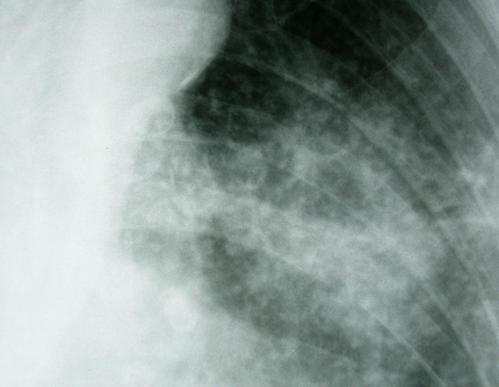

矽肺三期

矽肺三期,矽肺胸片

矽肺3期的影像图片

矽肺胸片

矽肺x光

矽肺影像

矽肺影像图片